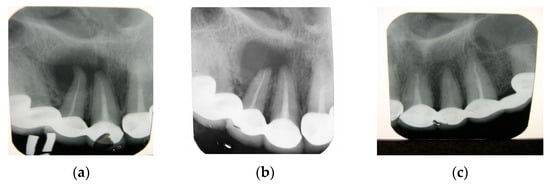

The use of the CH–SA construct (hydroxyapatite is not included in the copolymer molecule) in a clinical setting was performed in 30 patients aged 30–65 years after removal of a radicular cyst (15 people were operated on with implantation of a polysaccharide construct, and 15 people were used as controls, in whom the bone cavities were filled with a blood clot). All patients had bone defects of critical size after removal of the cyst. In addition, the polysaccharide implant was used in 13 patients aged 20–65 years after the removal of impacted teeth [74,75,76,77]. Studies have shown the high effectiveness of the CH–SA design in closing bone defects of critical size (Figure 8a–c).

Figure 8.

Radicular cyst of the patient’s left upper jaw (tooth 11.12): (a)—intraoral radiograph before surgery; (b)—intraoral radiograph 3 months after implantation of the CS–SA-structure, (c)—intraoral radiograph 6 months after implantation of the CS–SA-structure (complete restoration of the bone in the defect area, bone trabeculae are well traced).